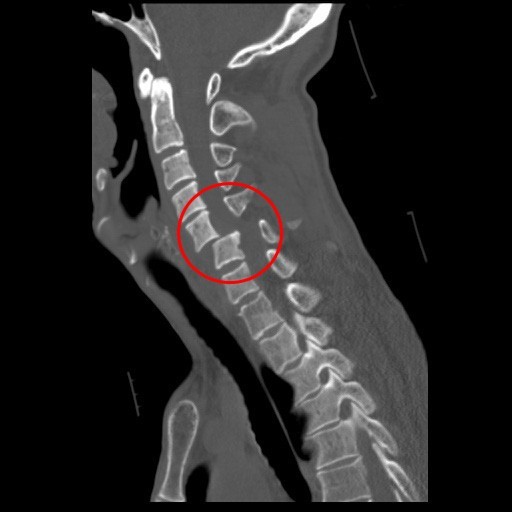

花蓮慈濟醫院神經脊椎微創外科主任洪祥益,指出宋先生的頸椎第五、六節骨折脫臼。

「當時身體沒有其他外傷,但雙手就是不聽使喚,無法動彈!」在轎車中受到劇烈撞擊的宋先生,只覺得頸椎劇痛。正逢休假期間的神經脊椎微創外科主任洪祥益一收到通知,就趕回醫院緊急為宋先生進行手術,洪祥益主任表示,宋先生的頸椎第五、六節骨折脫臼,如同竹子斷成兩截,其中脊髓神經受到擠壓幾乎快斷,所以導致雙手癱瘓。

宋先生的頸椎第五、六節骨折脫臼,如同竹子斷成兩截,其中脊髓神經受到擠壓幾乎快斷,導致雙手癱瘓。